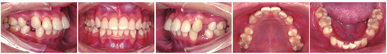

颌面部检查:面部左右基本对称,颏部略右偏,微笑时口角对称,牙列中线与面中线一致,上下唇前突,鼻唇角偏小,颏部发育可(图1)。

像口内检查:恒牙列18~27、37~47。上下中线基本对齐。上下前牙拥挤,尖牙及磨牙中性关系。牙体及牙周未见明显异常(图1)。